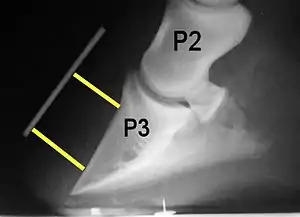

Radiograph of a horse hoof showing rotation of the coffin bone and evidence of sinking, a condition often associated with laminitis. The annotation P2 stands for the middle phalanx, or pastern bone, and P3 denotes the distal phalanx, or coffin bone. The yellow lines mark the distance between the top and bottom part of the coffin bone relative to the hoof wall, showing the distal (bottom) of the coffin bone is rotated away from the hoof wall.

Normally, the front of the third phalanx is parallel to the hoof wall and its lower surface should be roughly parallel to the ground surface. A single severe laminitic episode or repeated, less severe episodes can, depending upon the degree of separation of dermal and epidermal laminae, lead to either rotation or sinking of the pedal bone, both of which result in anatomical changes in the position of the coffin bone with visible separation of the laminae, colloquially known as founder. Rotation and distal displacement may occur in the same horse.[4] Both forms of displacement may lead to the coffin bone penetrating the sole. Penetration of the sole is not inherently fatal; many horses have been returned to service by aggressive treatment by a veterinarian and farrier, but the treatment is time-consuming, difficult and expensive.

Rotation is the most common form of displacement, and, in this case, the tip of the coffin bone rotates downward.[4] The degree of rotation may be influenced by the severity of the initial attack and the time of initiation and aggressiveness of treatment. A combination of forces (e.g. the tension of the deep digital flexor tendon and the weight of the horse) result in the deep digital flexor tendon literally pulling the dorsal face of the coffin bone away from the inside of the hoof wall, which allows the coffin bone to rotate. Also, ligaments attaching the collateral cartilages to the digit, primarily in the palmar portion of the foot, possibly contribute to a difference in support from front to back. The body weight of the animal probably contributes to rotation of the coffin bone. Rotation results in an obvious misalignment between PII (the short pastern bone) and PIII (the coffin bone). If rotation of the third phalanx continues, its tip can eventually penetrate the sole of the foot.